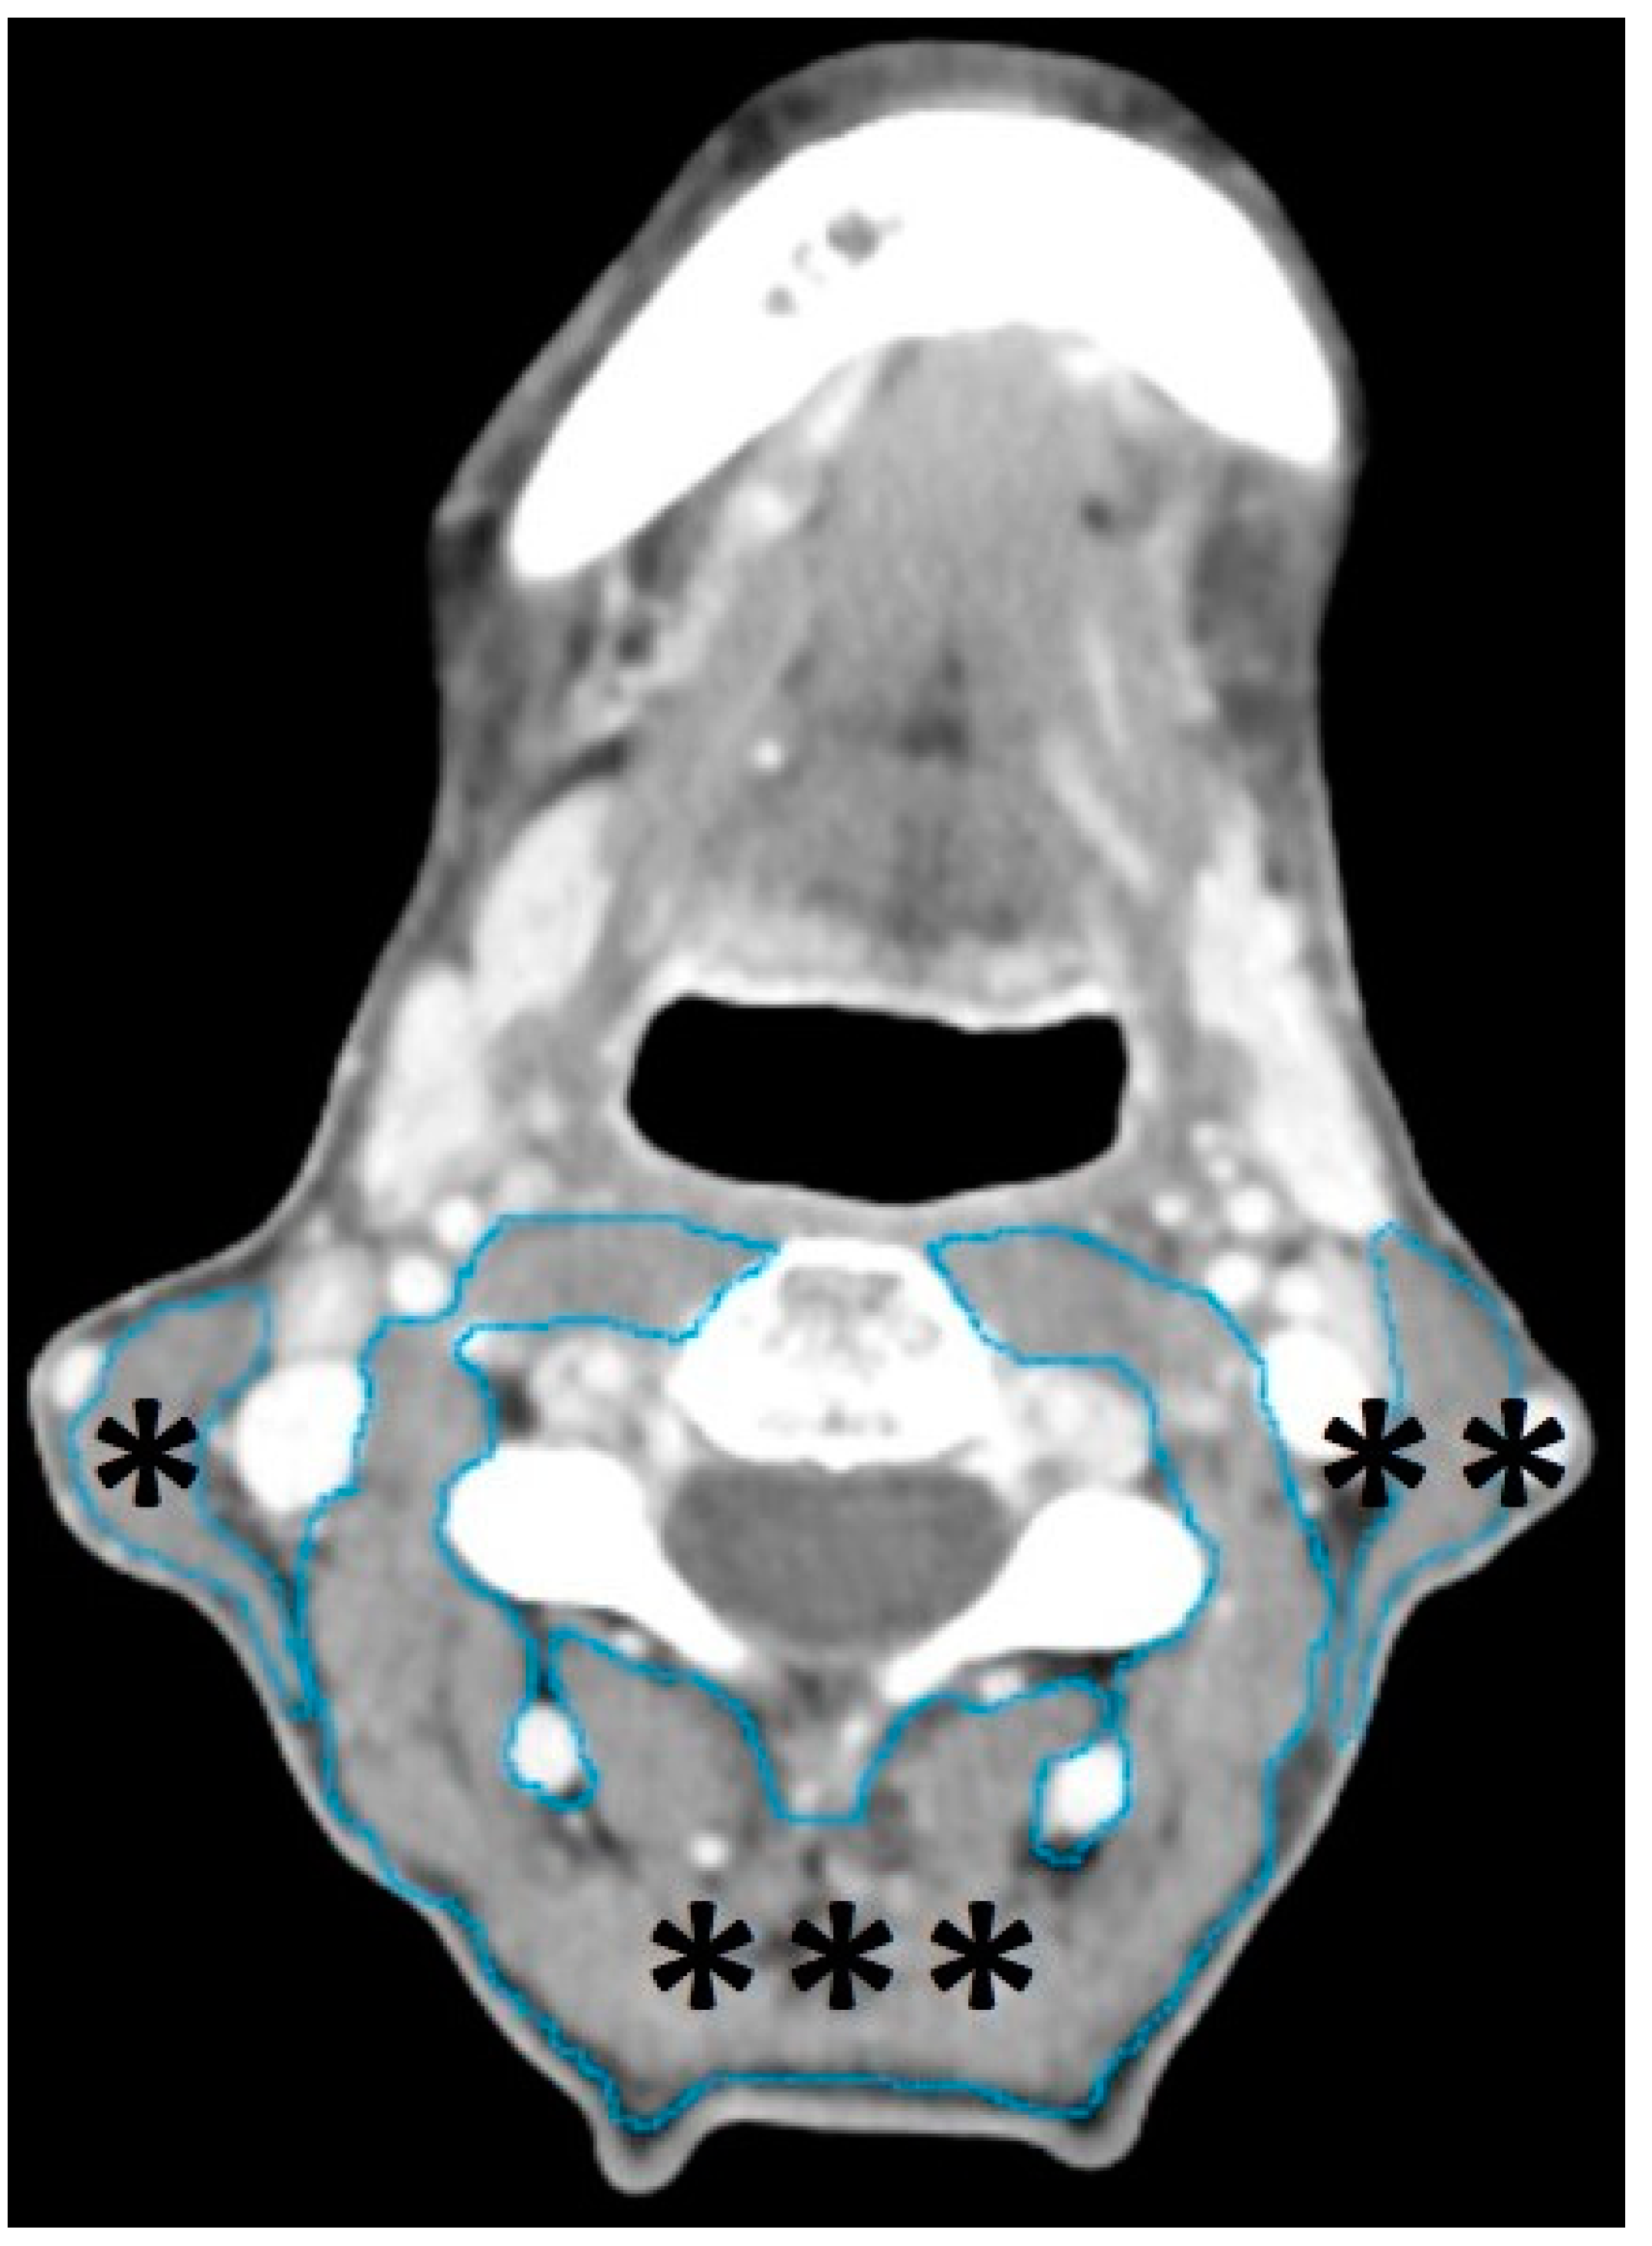

2.4. Segmentation of Head and Neck Musculature

2.5. Data Analysis